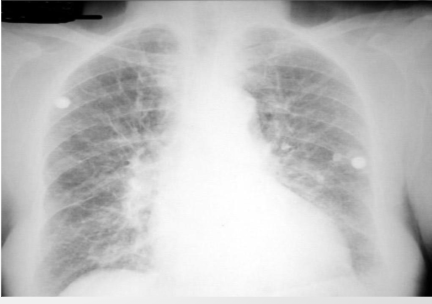

what is this?

cephalization of pulm vessels. first sign of congestive hf, phtn